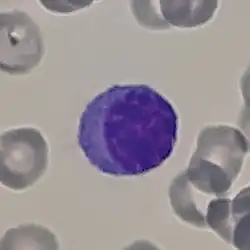

Imagen tomada con microscopio óptico de una célula plasmática teñida con hematoxilina-eosina. | ||

Las células plasmáticas son linfocitos grandes con una elevada proporción núcleo celular/ citoplasma y con un aspecto característico vistas al microscopio óptico. Tienen un citoplasma basófilo y un núcleo excéntrico con heterocromatina dispuesta en una característica forma de "rueda de carro". Su citoplasma también contiene una zona pálida que vista al microscopio electrónico contiene un extenso aparato de Golgi junto con los centriolos.[2] La abundancia de retículo endoplásmico rugoso combinada con un buen desarrollo del aparato de Golgi la hacen apta para la secreción de proteínas, en este caso inmunoglobulinas. El tipo de plasmocito descripto con estas características se denomina de tipo Marschalkó.